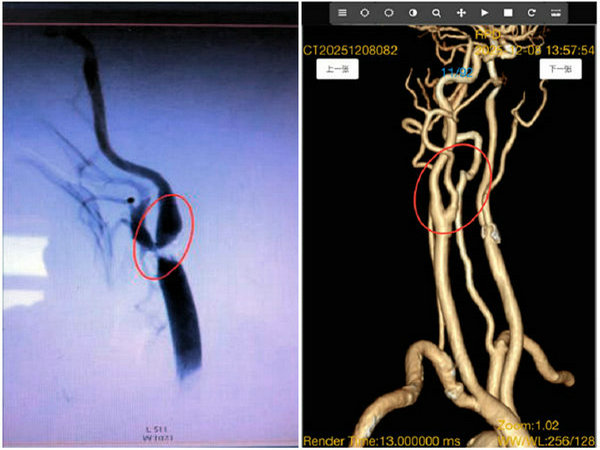

术前影像(血管狭窄) 术后影像(血管畅通)

脑血管健康是生命安全的重要基石,重度颈动脉狭窄犹如一颗“定时炸弹”,随时可能引发脑缺血、脑梗死等致命并发症。近期,王先生因身体不适就诊,经详细检查确诊为右侧颈内动脉起始段重度狭窄,血管通路严重受阻,随时面临脑卒中风险。面对危急病情与高龄患者的复杂身体状况,齐医附属二院迅速启动跨院协作机制,特邀在脑血管疾病外科治疗领域经验丰富的王洪军教授坐镇指导并主刀手术。

手术过程中,麻醉科主任孙宝文教授精准麻醉管理,电生理科主任韩国超实时监测保驾护航,王洪军教授凭借精湛的手术技艺与丰富的临床经验,协同刘增良教授、刘洋教授团队沉着操作,在高清视野下精准剥离堵塞血管的病变斑块,彻底清除血管通路障碍。整个手术流程规范、动作精准,有效规避了血管损伤、微栓子脱落等术中风险。术后影像学检查显示,王先生狭窄的颈内动脉血管恢复通畅,血流动力学指标完全正常,目前恢复良好,已顺利脱离脑血管疾病高危状态。